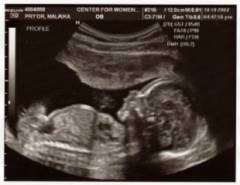

Заячью губу можно диагностировать с помощью ультразвукового исследования уже с 16 недели беременности. Некоторые специалисты утверждают, что хейлосхизис виден на УЗИ с 14 недели, но чаще всего аномалия выявляется в период с 4 по 5 месяц внутриутробного развития.

Первое плановое УЗИ проводится раньше (с 12 по 14 недели), поэтому увидеть сформировавшийся порок в этот период невозможно. Однако УЗИ-диагностика не всегда точна, так как интерпретация изображений может различаться у специалистов. Лишь 5-10% аномалий выявляется во время беременности, и чаще родители узнают о дефекте уже после родов.

Заячья губа может быть диагностирована с помощью ультразвукового исследования с 16 недели беременности. Некоторые эксперты утверждают, что хейлосхизис можно заметить уже с 14 недели, но чаще аномалия выявляется с 4 по 5 месяц внутриутробного развития.

Первое плановое ультразвуковое обследование проводится с 12 по 14 недели, поэтому в этот период невозможно обнаружить сформировавшийся порок. Последующая УЗИ-диагностика также не гарантирует точность из-за возможных ошибок в интерпретации изображений разными специалистами. Лишь 5-10% аномалий удается выявить во время беременности, и большинство родителей узнают о пороке только после рождения ребенка.